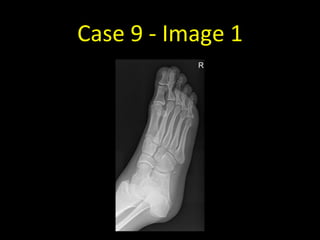

Case 9 - Image 1

Case 9

• No fracture!

• There is a boney density adjacent the

lateral cuneiform

• This is an accessory ossicle

• Note how rounded it appears, and it

doesn’t have the sharp edges of the

fractures in the previous cases

• Details of the common locations of